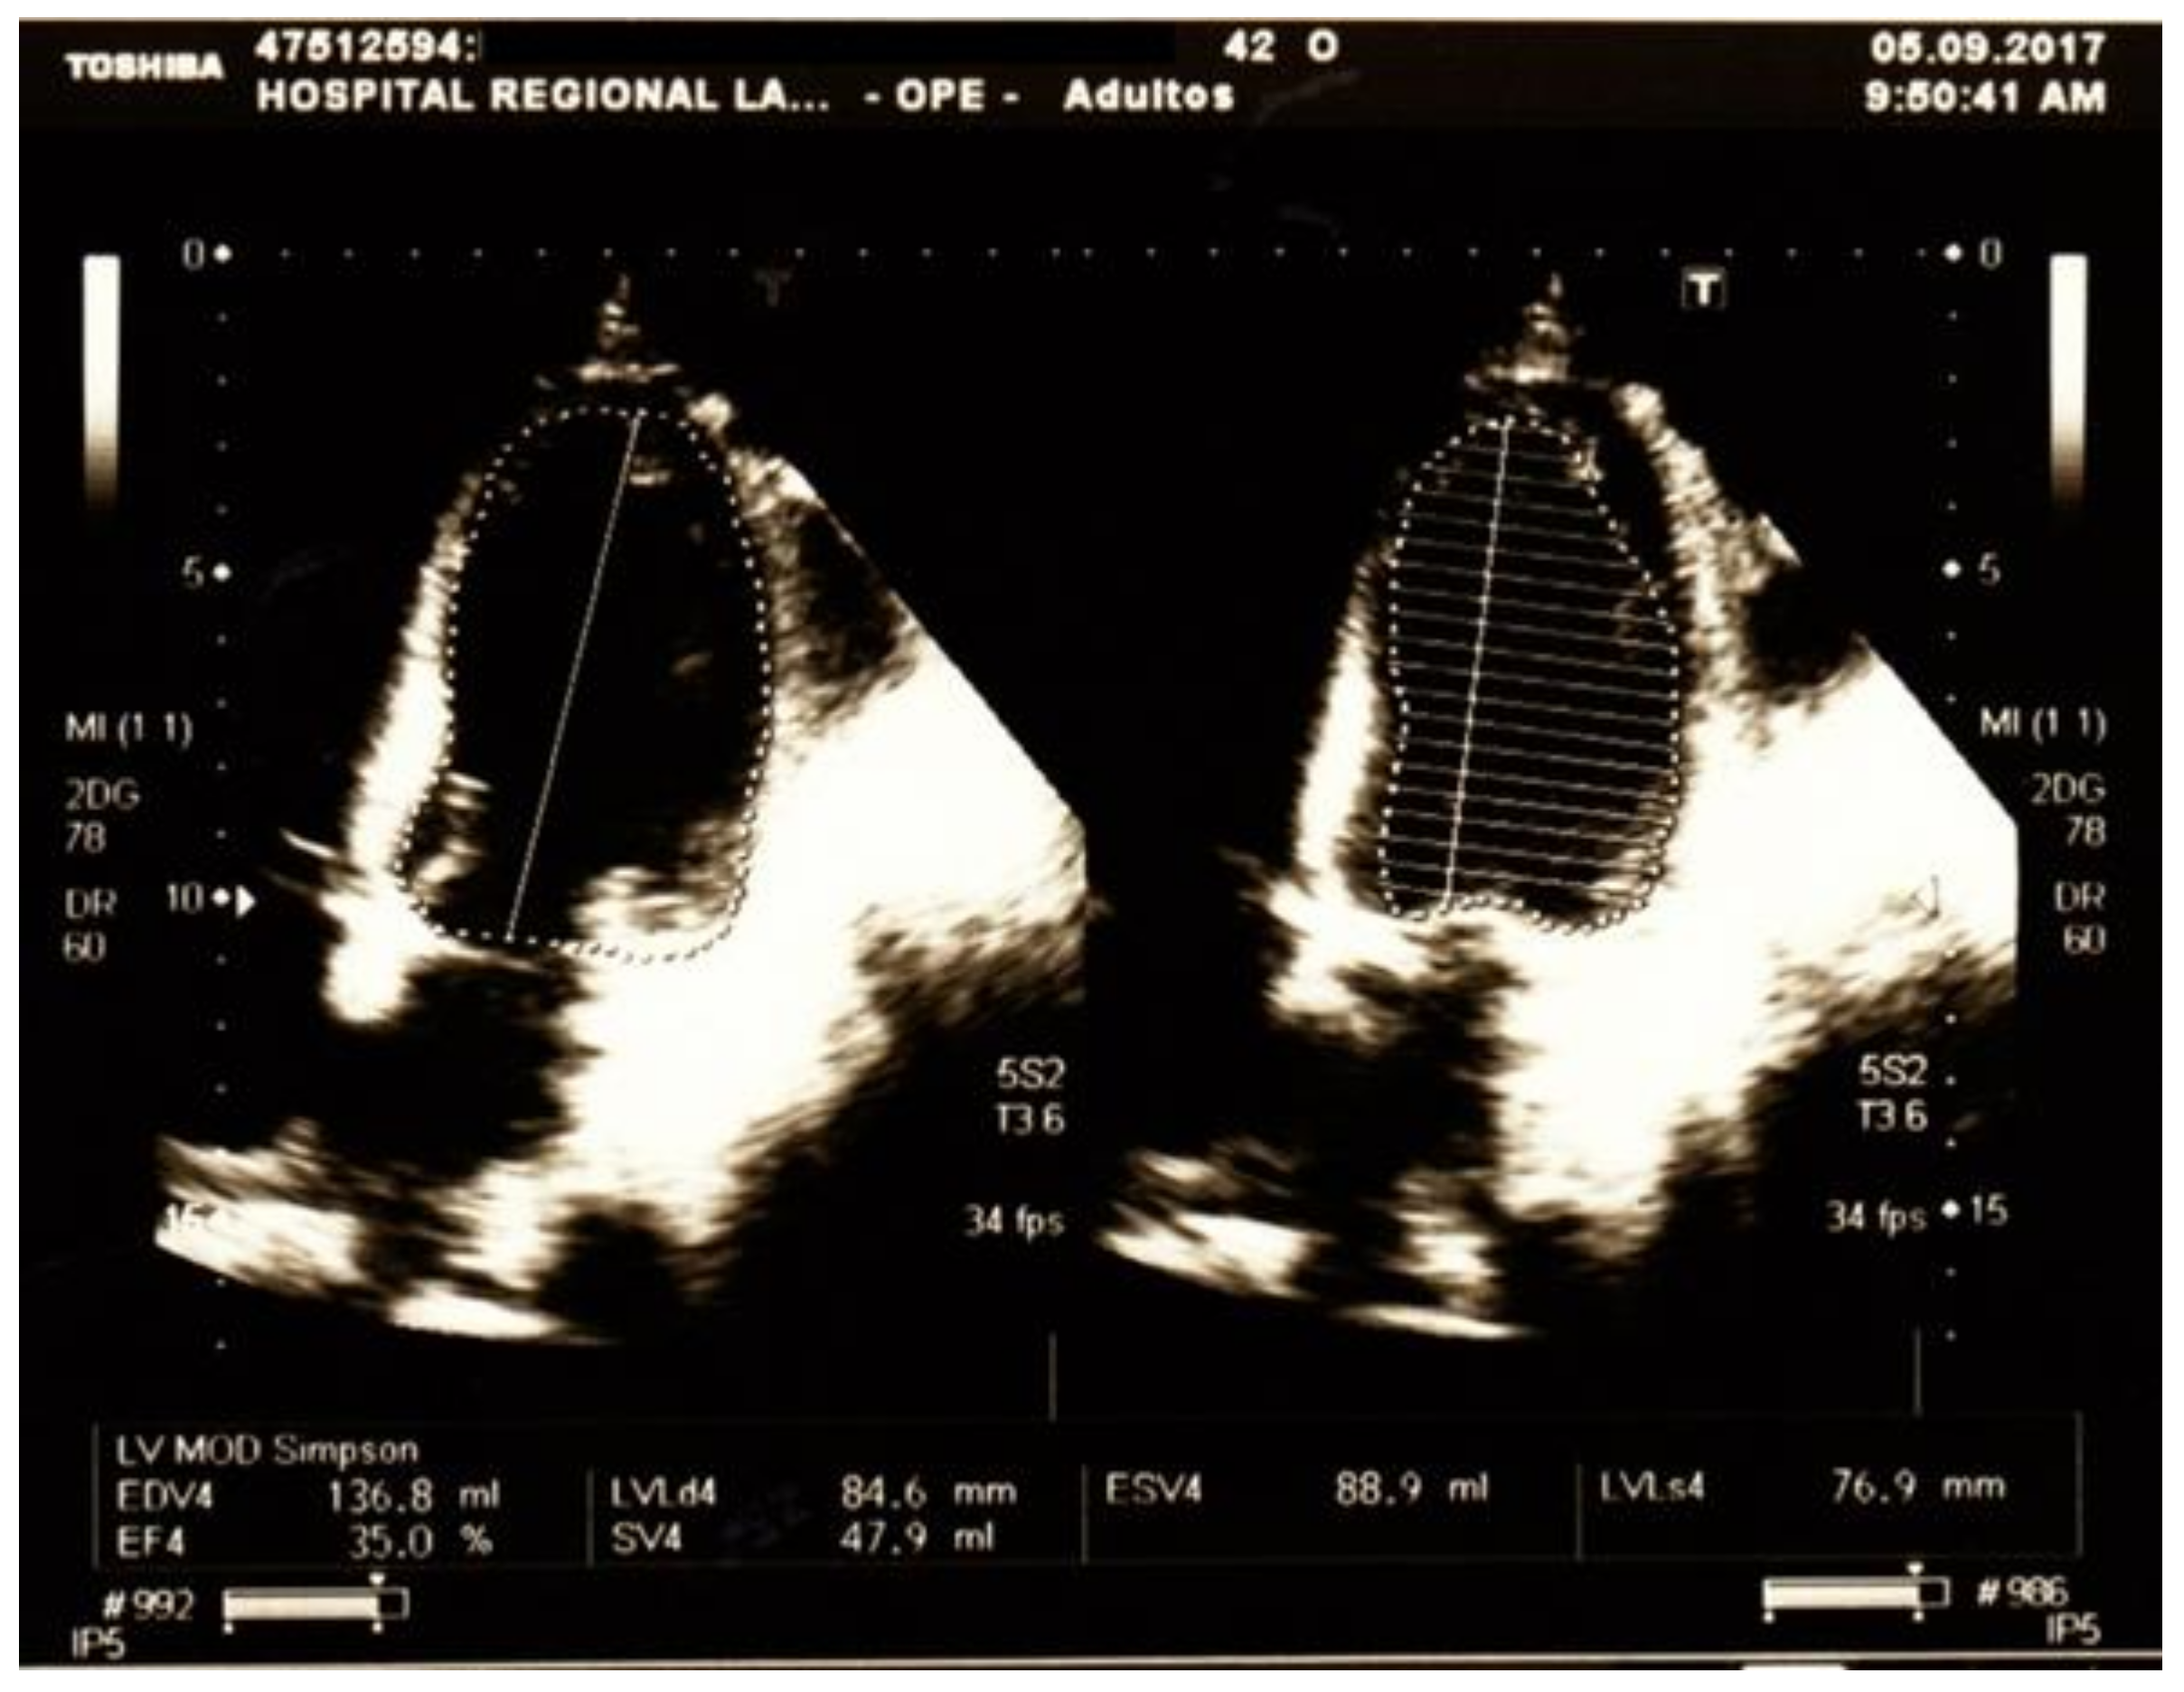

2. Case Presentation